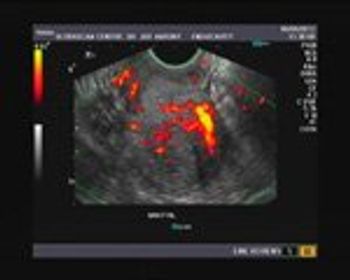

Our patient presents with a history of 5 weeks of amenorrhoea and scanty bleeding per vagina. Based on her history and ultrasound images, what is your diagnosis?